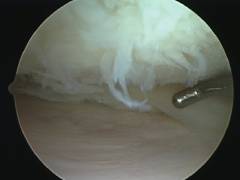

Артроскоп. Представляет собой разновидность эндоскопа, жесткую металлическую трубку толщиной 4-5 мм, в которой находится система линз. Это устройство позволяет получить изображение и вывести его на экран. К артроскопу подсоединяют световой кабель. -

Артроскопический зонд. Представляет собой изогнутый металлический стержень. При помощи него хирург может отодвинуть различные структуры, чтобы лучше осмотреть полость сустава. На артроскопическом зонде нанесены метки, благодаря которым можно оценить размеры образований. - Различные эндоскопические инструменты.

- Первым в полость коленного сустава вводят артроскоп. Хирург делает надрез на коже скальпелем, а затем прокалывает подкожный жир и суставную капсулу при помощи троакара, и попадает в полость сустава.

- Обычно вместе с основным проколом делают еще два. Через них можно ввести инструменты и канюлю для промывания сустава. Всего в области коленного сустава существует 8 точек, в которых могут быть сделаны проколы во время артроскопии.

- Врач последовательно осматривает все внутрисуставные структуры. При необходимости может быть проведена артроскопическая операция.